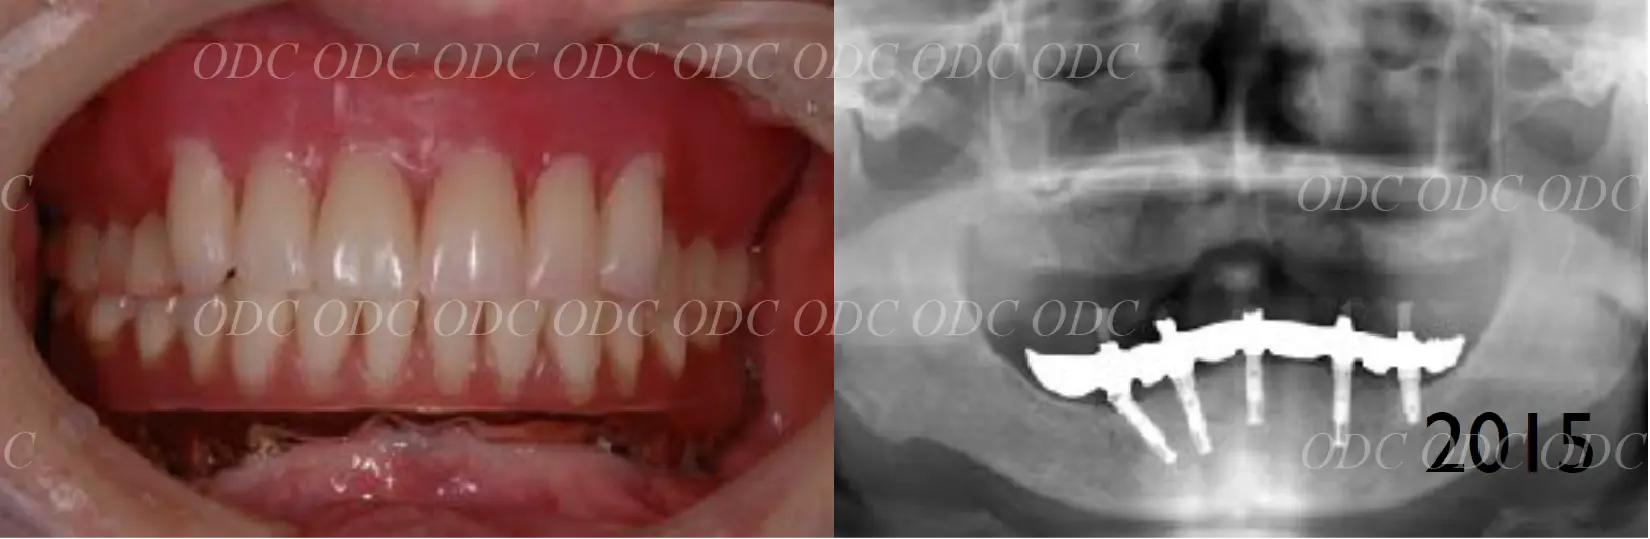

前歯部多数歯欠損症例

2010年、前歯5本欠損でインプラント治療を希望されて来院されました。

インプラント埋入後、プロビジョナルレストレーションにて軟組織のスキャロッピングを行います。

咬合状態に問題無いことを確認後、CADCAMのメタルフレームにセラミックを築成して治療終了。

最終補綴装着時の口腔内写真です。スクリュー固定でアクセスホールが理想的な位置に存在します。

顎関節等の噛み合わせ治療を併用して上下固定式のインプラント治療を終了。

上顎には第3世代ジルコニアの上部構造、下顎には第2世代セラミックの上部構造を装着。

タカギインデックスより計算された咬合平面を設定しているため、噛み合わせはとても安定しております。

治療終了より約11年経過しましたが現在も問題なく使用されています。

サイナスリフトした骨も全てのインプラント体も安定しております。